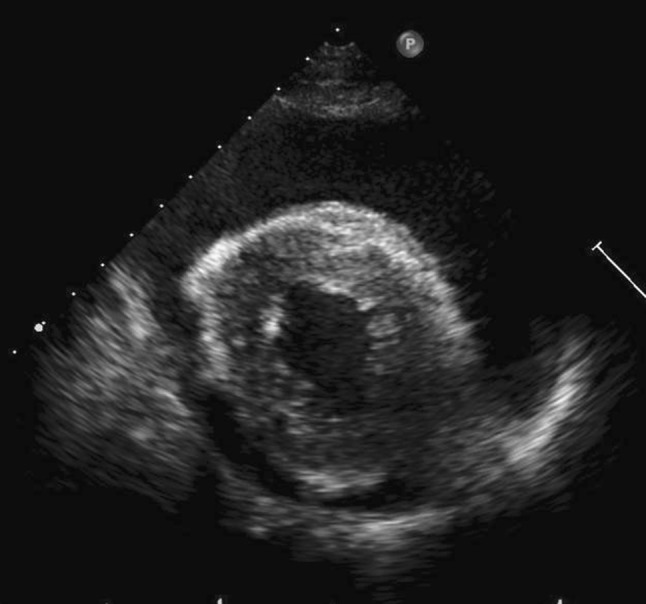

Fig. 6.

Transthoracic echocardiography in the short axis view shows a large amount of pericardial effusion

Four years after CRT, the patient was re-admitted to our hospital with complaints of dyspnea and heart palpitations on exertion. Chest radiography and computed tomography (CT) revealed a large amount of pleural effusion on the left side (Figs. 4a, 5a), without metastasis or pneumonitis (Fig. 5b). Transthoracic echocardiography showed a large pericardial effusion with slight decrease in the left ventricular ejection fraction (Fig. 6). Thoracentesis on the left side and pericardiocentesis were performed, and the volume of effusion removed was 1300 and 400 ml, respectively. Drained fluid was clear and serous; cytological examination was negative for bacteria and cancer cells. Blood examination showed that tumor marker levels of carcinoembryonic antigen (CEA) and squamous cell carcinoma-related antigen (SCC) were not elevated. Slight hypoalbuminemia was noted; liver transaminase was elevated slightly. Blood urea nitrogen and creatinine levels were within the normal ranges; protein was not detected in the urine. Serum thyroid-stimulating hormone (TSH) level was elevated slightly in the context of normal thyroid hormone level. These laboratory data are shown in Table 1. For subclinical hypothyroidism, 50 μg/day of levothyroxine was administrated orally. Autoimmune disease and infections, including tuberculosis, were ruled out. Cardiac function, after draining pericardial effusion, was normal when re-assessed by echocardiography. The pleural and pericardial effusions were suspected to be late toxicities caused by CRT. Initially, loop diuretic agent (20 mg/day) and an aldosterone antagonist (25 mg/day) were administrated orally. Pericardial effusion was controlled well; however, pleural effusion was not and required additional drainage twice for 2 months. We prescribed 30 mg/day of oral prednisolone (equivalent to 0.57 mg/kg/day), with diuretic agents administered concurrently. Prednisolone was continued and tapered for 4 additional months, without refractory pleural effusion. After 5.0 mg/day of prednisolone was administered, the patient complained of dyspnea; chest radiography revealed pleural effusion. We increased the prednisolone dose to 7.5 mg/day, and more gradually tapered it. Although the diuretic agents are still administered, prednisolone was no longer administered for 3 and half years after the first pleural effusion. A small amount of pleural effusion remains in the left thoracic cavity (Fig. 3b), but the patient is free from respiratory symptoms.